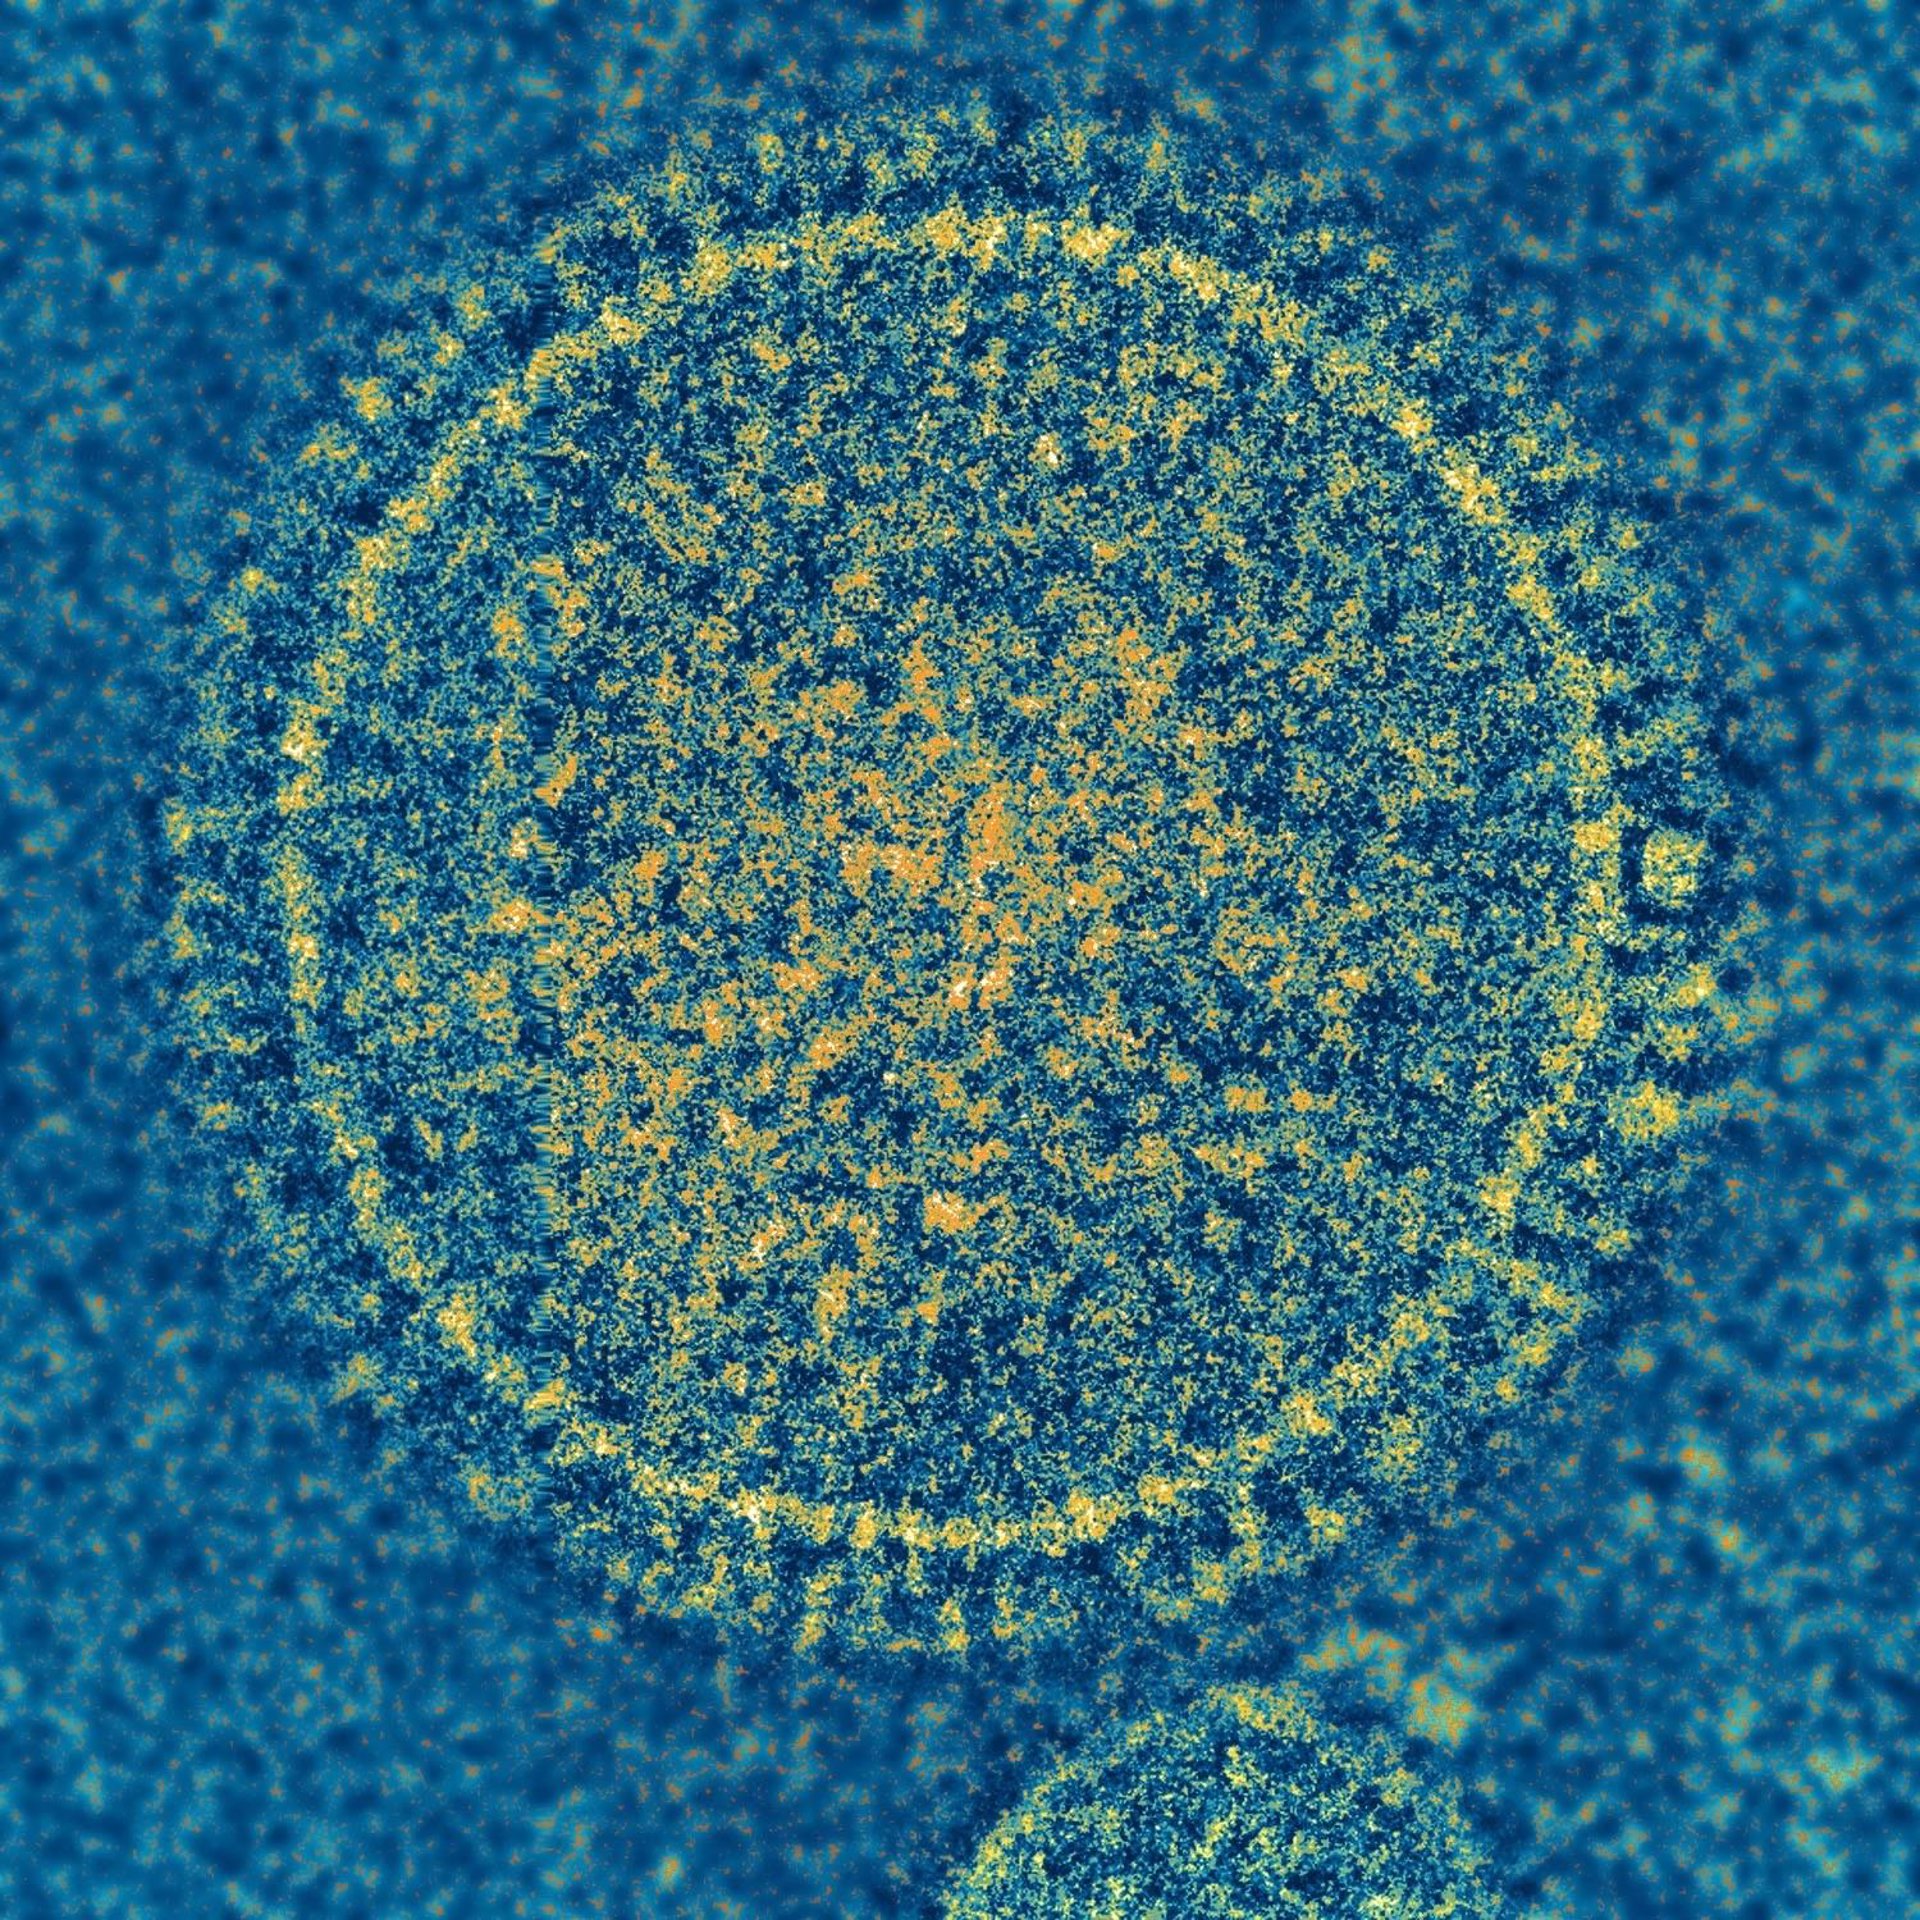

Cuando se evaluaron a través de microscopía electrónica, los viriones OE4 se parecían a los viriones estándar del VRS, excepto que OE4 presentaba niveles más altos de la forma inmunogénica de la proteína F y niveles más bajos de otra proteína llamada G. El trabajo de microscopía electrónica fue una colaboración con Elizabeth Wright, profesora asociada de Pediatría y coautora principal en el trabajo, y sus colegas.